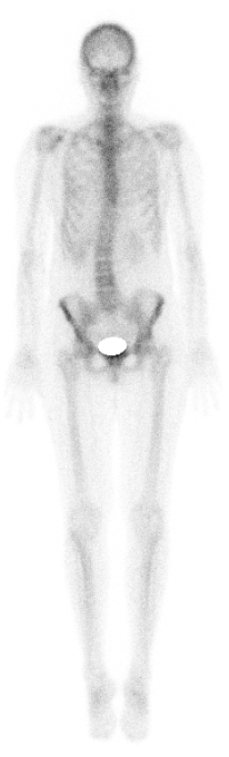

Entzündungsszintigraphie

Hierbei werden spezielle Zellen markiert, die bei Entzündungen gehäuft auftreten (z. B. Granulozyten). Diese können dann dargestellt werden bspw. wenn die Entzündungsursache nicht klar ist. Für viele Fragestellungen bzgl. Entzündungssuche ist jedoch die FDG-PET/CT die genauere Untersuchung, wir informieren Sie gern.